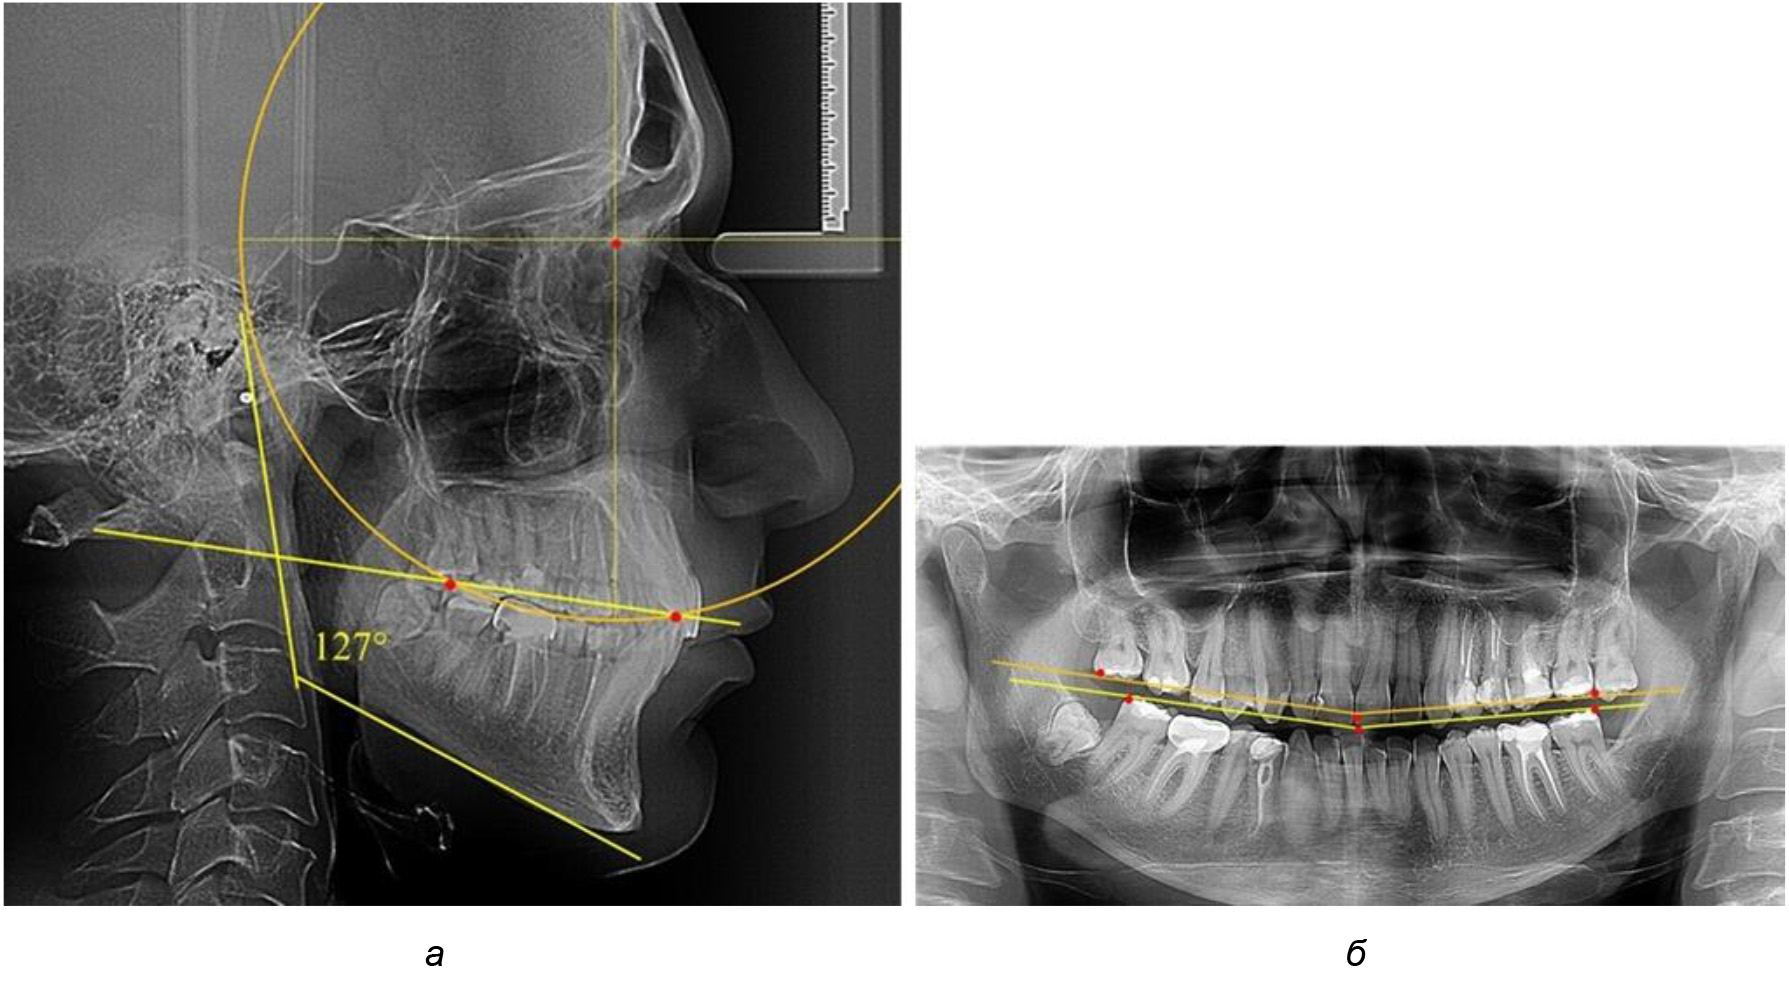

У людей с аномалиями окклюзии по сагиттали в 1-й подгруппе обследовано 9 человек. Обращает на себя внимание увеличение глубины кривой Spee, что нами расценивалось, как патологическая форма кривой линии окклюзии.

Глубина кривой Spee в среднем по 2-й подгруппе составила (5,69 ± 1,57) мм, что было достоверно больше, чем у людей с физиологической окклюзией (р ˂ 0,05). Достоверных различий с показателями, полученными при анализе ТРГ и ОПТГ, нами не отмечено (р ˃ 0,05). Отношение радиуса окружности к сагиттальному размеру окклюзионной линии в среднем по подгруппе составляло 1,372 ± 0,042 и не соответствовало числу Фибоначчи, что может быть использовано в качестве диагностического критерия определения патологической формы кривой Spee. После лечения пациентов техникой «прямой» дуги было отмечено незначительное увеличение сагиттального размера окклюзионной лини в среднем на (2,12 ± 0,77) мм. Однако окклюзионная линия практически касалась окклюзионного контура всех жевательных зубов, и отмечалось практически полное отсутствие кривой Spee.

Таким образом, проведенное лечение техникой «прямой» дуги способствует нормализации окклюзионного равновесия и торку передних зубов, однако не соответствует оптимальному окклюзионному статусу, характеризующему физиологическую окклюзию. При этом величина нижнечелюстного угла оставалась на прежнем уровне (рис. 5).

Рис. 5. Особенности ТРГ при патологической кривой Spee до лечения (а) и после лечения (б) техникой «прямой» дуги

После лечения пациентов техникой «прямой» дуги, так же как и в 1-й подгруппе, было отмечено увеличение сагиттального размера окклюзионной лини в среднем на (2,38 ± 0,83) мм. Окклюзионная линия практически касалась окклюзионного контура всех жевательных зубов, и отмечалось практически полное отсутствие кривой Spee, так же как и у людей 1-й подгруппы 2-й группы (рис. 6).

Рис. 6. Особенности ТРГ при оптимальной кривой Spee до лечения (а) и после лечения (б) техникой «прямой» дуги

Таким образом, проведенное лечение техникой «прямой» дуги способствует нормализации окклюзионного равновесия и торку передних зубов, однако не соответствует оптимальному окклюзионному статусу, характеризующему физиологическую окклюзию. При этом величина нижнечелюстного угла оставалась на прежнем уровне.